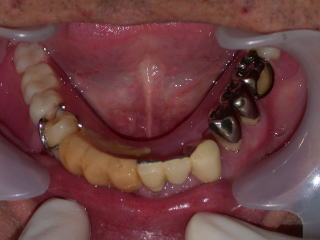

下の義歯はバネのないクラスプレス義歯です。